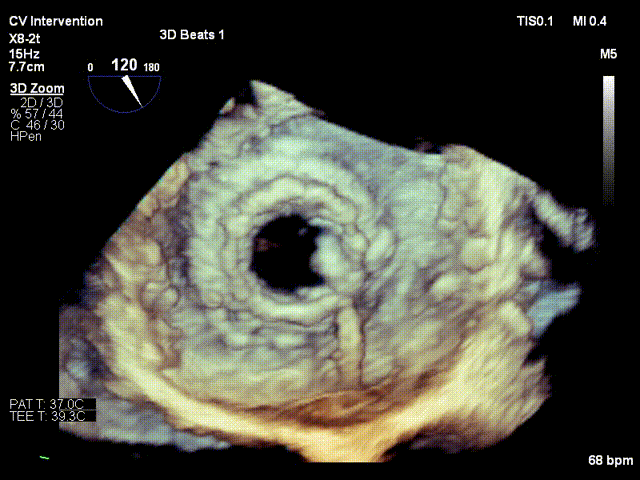

患者手术过程顺利,穿刺右侧股动脉作为TAVR路径,右侧股静脉作为TMVR路径。通过食道超声指引房间隔穿刺,在卵圆窝偏下后方位置顺利进入左房,留置钢丝后全身肝素化;通过右侧股动脉植入20F GORE鞘,按照常规TAVR流程,在主动脉瓣成功进行人工主动脉植入,测定术后压差为0 mmHg。然后通过左房留置钢丝交换可调弯鞘,帮助顺利跨瓣,再次将鞘交换为14 F E-sheath后,在二尖瓣生物瓣位置顺利完成瓣中瓣植入,术后即刻二尖瓣平均跨瓣压差降至4 mmHg。双瓣置换手术成功完成。